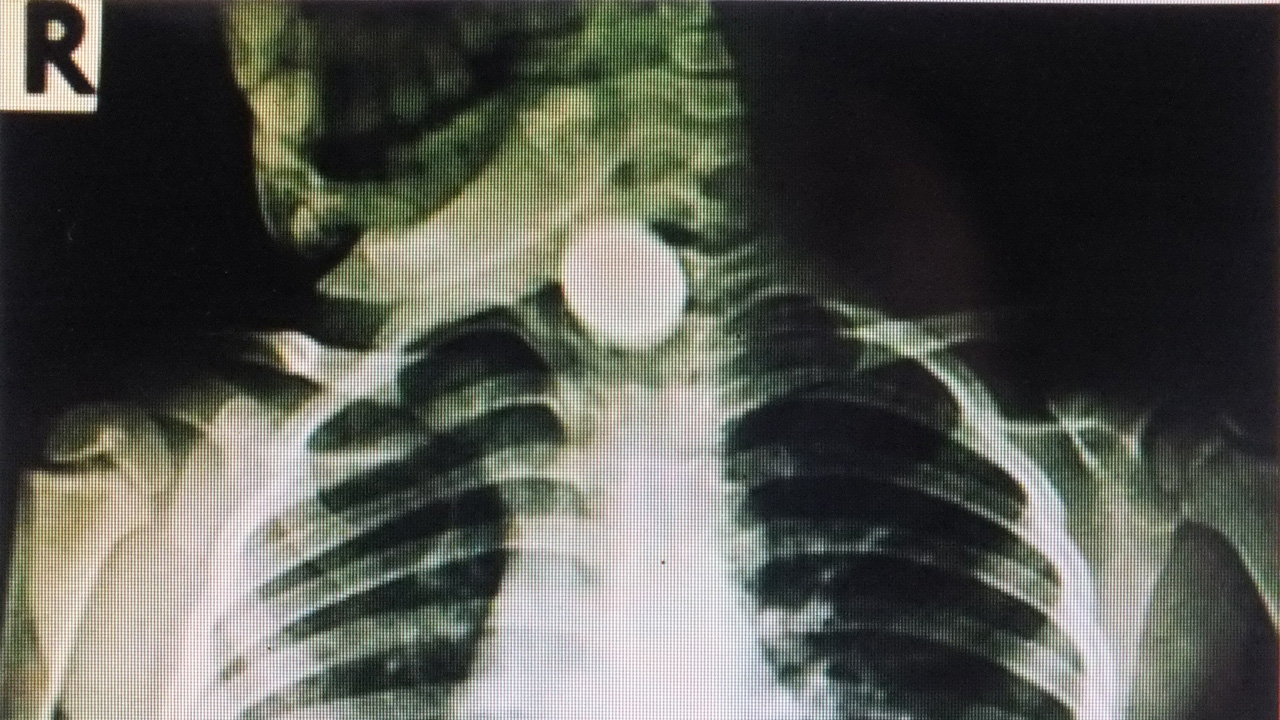

จากการตรวจสอบเบื้องต้นพบว่า มีเหรียญติดที่ลำคอ เด็กมีสีหน้าที่บ่งบอกถึงความเจ็บปวดและมีคราบน้ำตาเปื้อนอยู่ ใกล้ๆ กันพบกับนางทองเพชร คู่กระสังข์ อายุ 58 ปี อยู่บ้านเลขที่ 92 บ้านหัวนาคำ หมู่ 4 ต.ดงกลาง อ.จตุรพักตรพิมาน ซึ่งกำลังนั่งอุ้มเด็กหญิงหล่าอยู่

ต่อมา นางทองเพชร ชงเครื่องดื่มโอวัลตินให้ ด.ญ.หล่า กินก่อนที่จะนอนกลางวัน หลังจากโอวัลตินหมดขวดแล้ว จากนั้น ด.ญ.หล่าร้องไห้เเละมาบอกกับตนว่าเจ็บคอ เพราะก่อนหน้านั้นขณะเล่นอยู่กับเพื่อน เอาเงินเหรียญหนึ่งบาทอมไว้ในปาก จึงกลืนลงไปในลำคอพร้อมกับน้ำโอวัลติน ต่อมา นางทองเพชรจึงบอกให้เพื่อนบ้านมาหาทางช่วย เอามือล้วงคอ ด.ญ.หล่า แต่ก็ไม่สำเร็จ จึงตัดสินใจรีบนำส่ง รพ.จตุรพักตรพิมาน ตรวจรักษา ก่อนส่งต่อ รพ.ร้อยเอ็ด รักษา